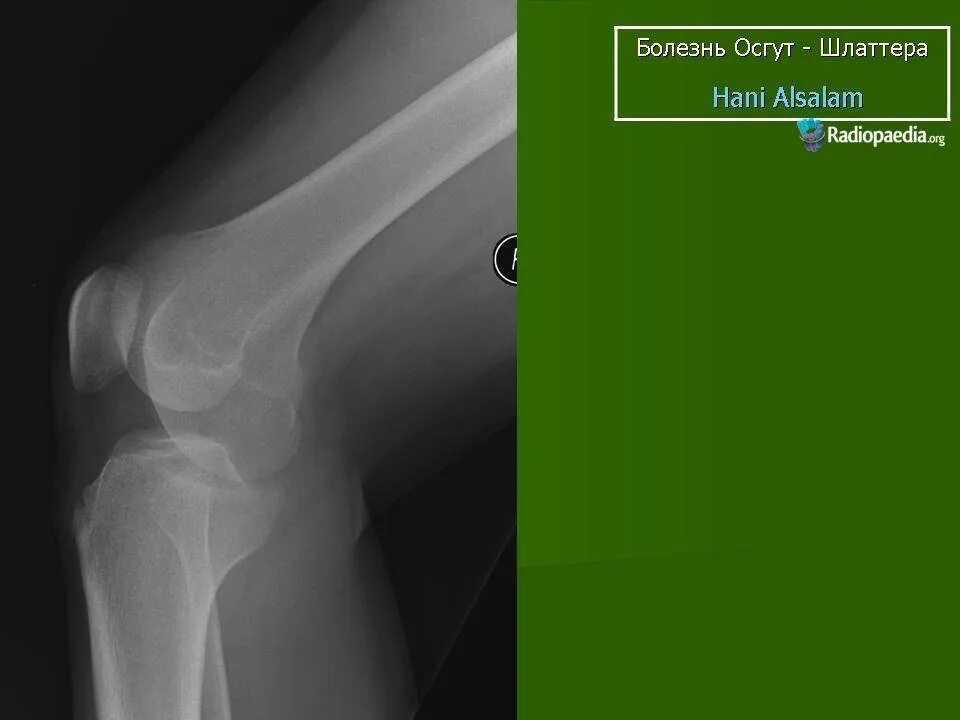

Код мкб шляттера